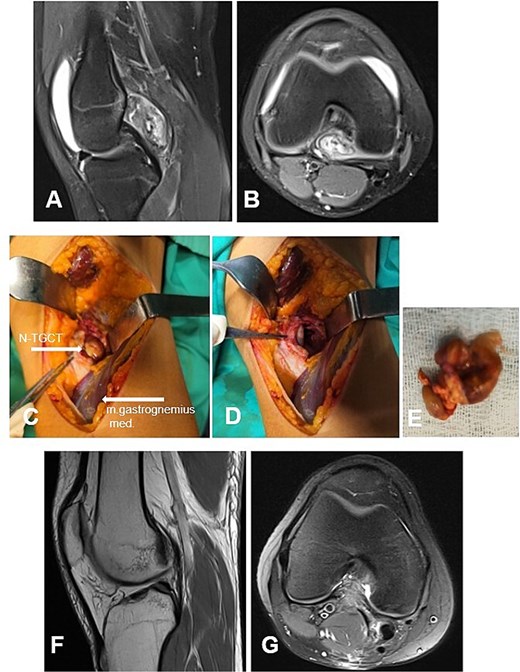

Case 3

A 6-year-old girl with a 3-year history of knee pain and swelling, previously treated for Synovitis transitoria. The chronic course of the condition corresponded to progressive limitation of flexion and the development of a flexion contracture (Table 1). The diagnosis was established by MRI (Fig. 4A and B). The D-TGCT involved the central, superior, and inferior infrapatellar synovial recesses (Fig. 4C). Through open synovectomy, the visibly altered synovium was excised en bloc (Fig. 3D and E). The hyaline cartilage changes were classified as grade I according to Outerbridge. One year after surgery, the child remained asymptomatic with a full range of motion in the knee. MRI showed no evidence of recurrence of the excised neoplasm (Fig. 3F and G).

Case 3. (A and B) Preoperative sag and ax MRI TSE PD FS. (C and E) Macroscopic appearance of the pathological synovium before and after its excision. (D) The knee joint following synovectomy. Chondral lesions correspond to Outerbridge grade I. (F and G) Postoperative 12 m. Sag and Ax MRI TSE PD FS—no evidence of recurrence of the resected neoplasm. PD FS, proton density weighting with fat suppression; TSE, turbo spin echo.